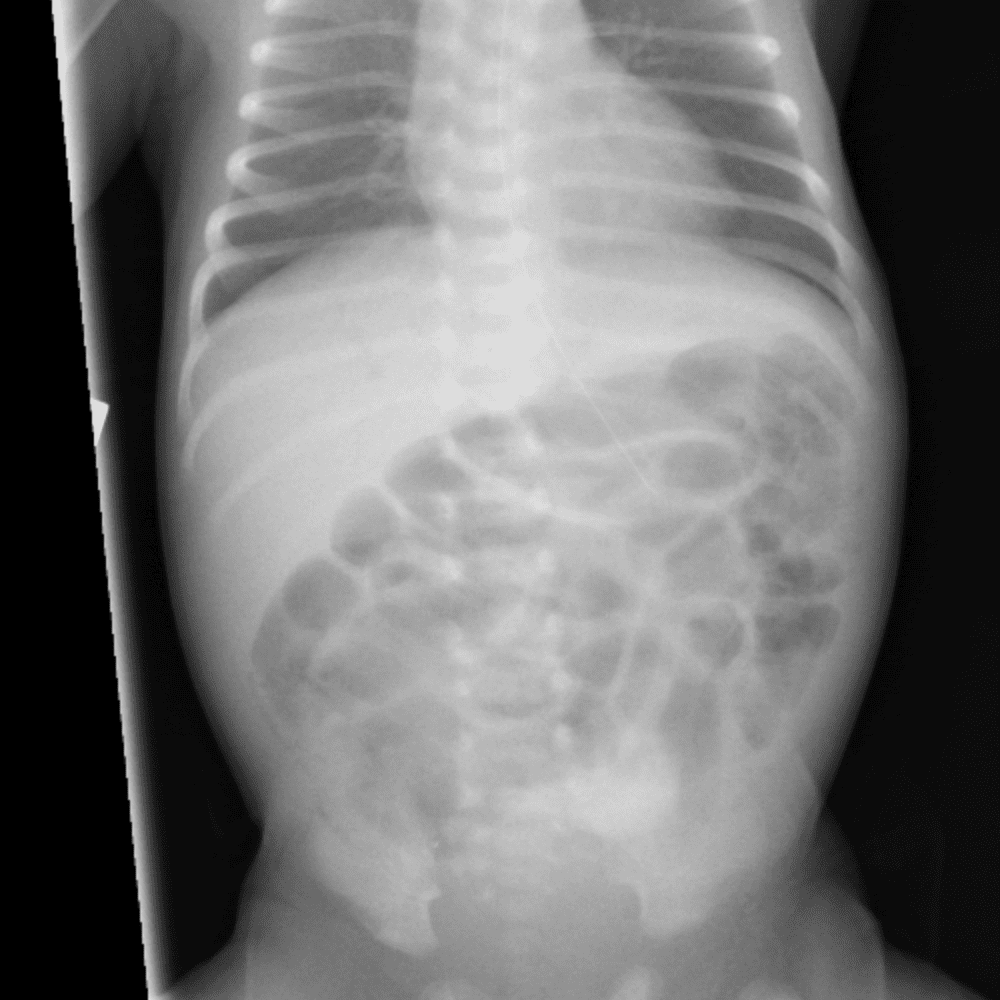

Peds Abdomen

Practice

Simulates call by including subtle or difficult cases and some normals.

30 cases